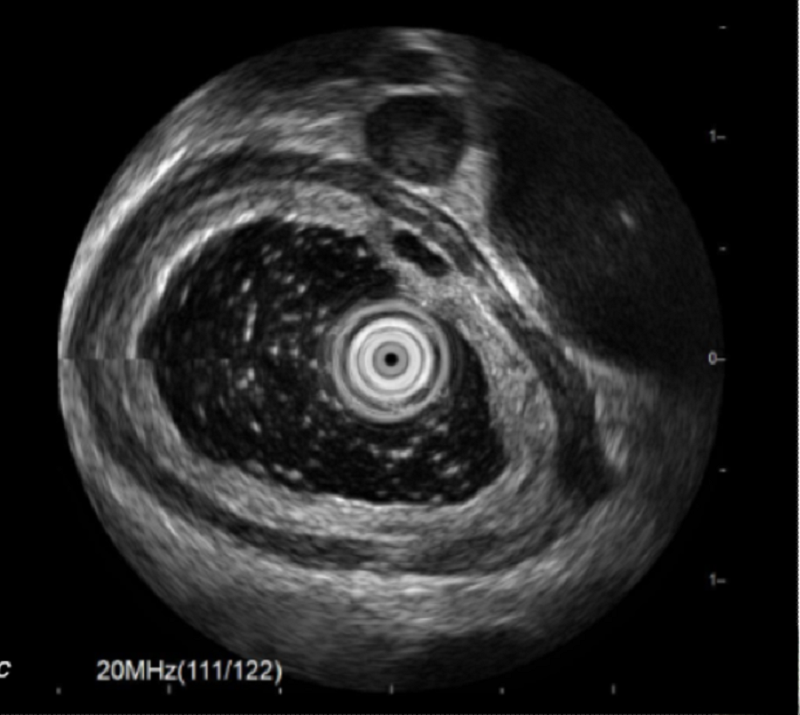

Phát hiện khối u ở thực quản nhờ... uống bia- Ảnh 2.

Nội soi siêu âm cho thấy hình ảnh u dưới niêm mạc xuất phát từ lớp cơ niêm, theo dõi u cơ trơn

Nội soi siêu âm cho thấy khối u kích thước khoảng 0.5x0.2x0.7cm, giảm âm đồng nhất, ranh giới rõ, nằm ở lớp cơ niêm, không thấy chảy máu, vôi hóa trong u.

Dựa vào kết quả trên, anh A. được chẩn đoán xác định u dưới niêm mạc thực quản xuất phát từ lớp cơ niêm theo dõi u cơ trơn (Leiomyoma).

Trường hợp bệnh nhân A., trên nội soi siêu âm có khối u ở lớp cơ niêm của thực quản, giảm âm đồng nhất, giống tính chất lớp cơ. Đây là hình ảnh đặc trưng u cơ trơn, chưa có đặc điểm gì gợi ý ác tính (vôi hóa, chảy máu, loét bề mặt, nhú lồi trong u...).